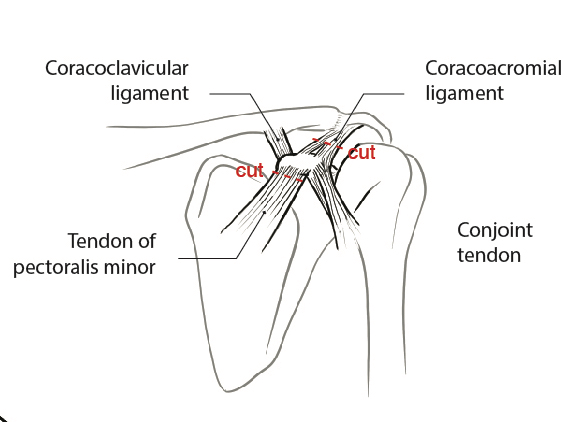

Coracoid osteotomy

- use retractor on superior surface to identify entire coracoid

- release coracoacromial ligament from lateral coracoid

- release pectoralis minor from medial coracoid

- mobiize conjoint tendon, beware MCN 5 cm distal